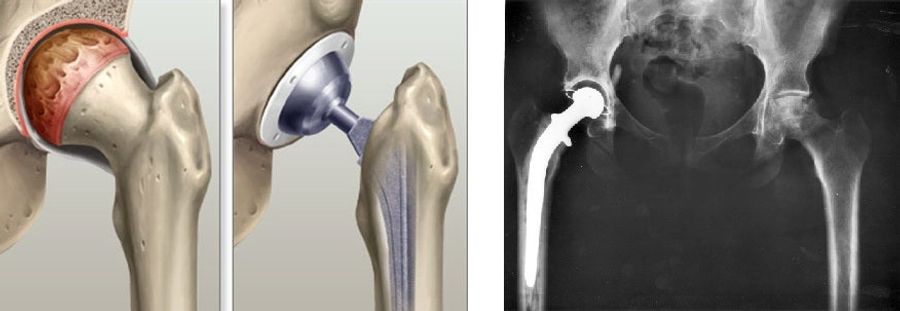

But even if caught and treated, the prognosis for avascular necrosis of the hip is poor. Treatment may prolong joint viability, but a hip replacement is in the future. Replacements involve artificial acetabulums and femur heads grafted into the patient's femur and pelvis. Strength and lifespan of replacements are constantly improving, often as a result of new materials. They've developed from the "simple" cobalt-chromium alloys of the past to the ceramic, polyethylene, and zirconia-crystal embedded alumina of today, minimizing both particle-producing wear and fracture propagation. Biomechanical improvements are occurring as well. One elegant adjustment for more athletic patients was to increase the diameter of the graft ball. The larger surface for rotation increases the range of motion possible before risking dislocation.7 Still, it's a far cry from a real, functioning hip for a professional athlete.